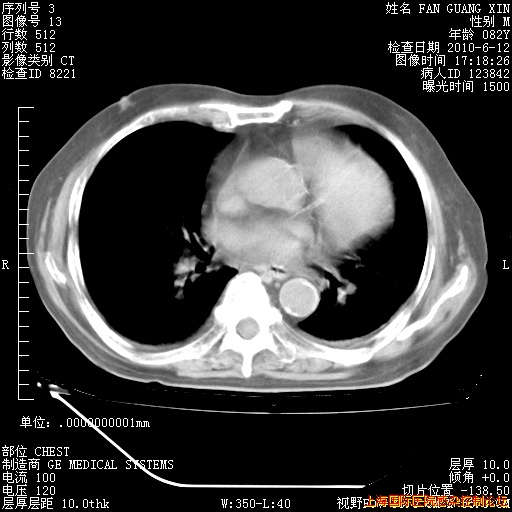

6月12日纵膈窗